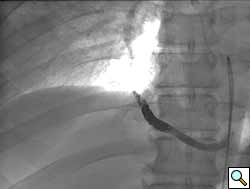

A previously healthy 43-year-old male presented with cough, fevers, and leukocytosis. A chest radiograph (Figure 1) revealed extensive consolidation in the right lower lung containing multiple cavities with air-fluid levels consistent with a necrotizing infection. A chest computed tomogram (Figure 2) showed an abscess cavity and consolidation in the right lower lobe with an aberrant blood supply from the descending aorta. This systemic blood supply was confirmed by subsequent 3D reconstruction (Figure 3). He was initially treated with IV antibiotics, resulting in normalization of his temperature and white blood cell count. He was then discharged home on a 3-week course of oral antibiotics. Three days prior to a planned surgical resection, he underwent angiographic localization of the feeding artery (Figure 4) and coil embolization (Figure 5).

To prevent complications from infection, hemorrhage, and possible malignancy, surgical resection of ILS is recommended [7]. Preoperative coil embolization of the arterial supply can decrease the risk of hemorrhagic complications and has been reported in the pediatric literature as an alternative to surgery [8]. However, intraoperative vascular control of this vessel may be more difficult if the coils are positioned in the artery outside of the sequestration rather than within the sequestration. Operative approaches involving thoracoscopy and thoracotomy have been reported, utilizing lobectomy, sequestrectomy, and wedge resection [9]. A recent review found pediatric and adult ILS anatomy, presentation, and treatment options to be similar [10].